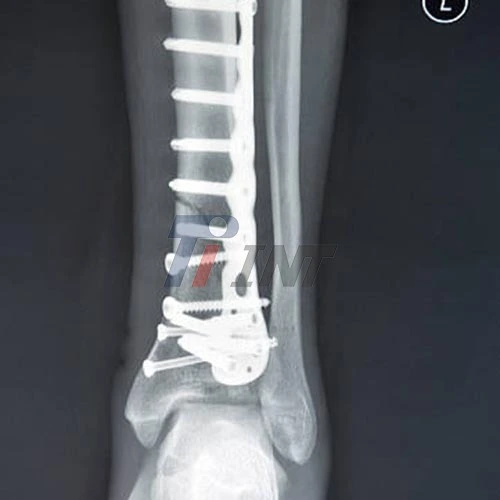

The 3mm titanium plate boasts an impressive strength-to-weight ratio, making it an optimal choice for bone fixation. This property allows surgeons to use thinner plates without compromising on structural integrity. The high strength of titanium ensures that the plate can withstand the stresses of daily activities and provide stable fixation for fractured bones.

Moreover, the strength of titanium plates allows for greater flexibility in surgical techniques. Surgeons can bend and contour these plates to match the specific anatomy of each patient, ensuring a precise fit and optimal bone alignment. This adaptability is crucial in complex fracture cases where standard plate shapes may not suffice.

Customization Capabilities for Optimal Surgical Outcomes

The versatility of 3mm titanium plates extends to their customization potential. Manufacturers can produce these plates in various shapes and sizes to accommodate different bone structures and fracture patterns. This customization capability allows surgeons to select the most appropriate plate for each specific case, optimizing the fixation strategy and improving surgical outcomes.

Advanced manufacturing techniques, such as 3D printing, have further expanded the customization possibilities for titanium plates. These technologies enable the production of patient-specific implants that perfectly match the individual's anatomy, potentially leading to better fit, faster healing, and improved functional recovery.